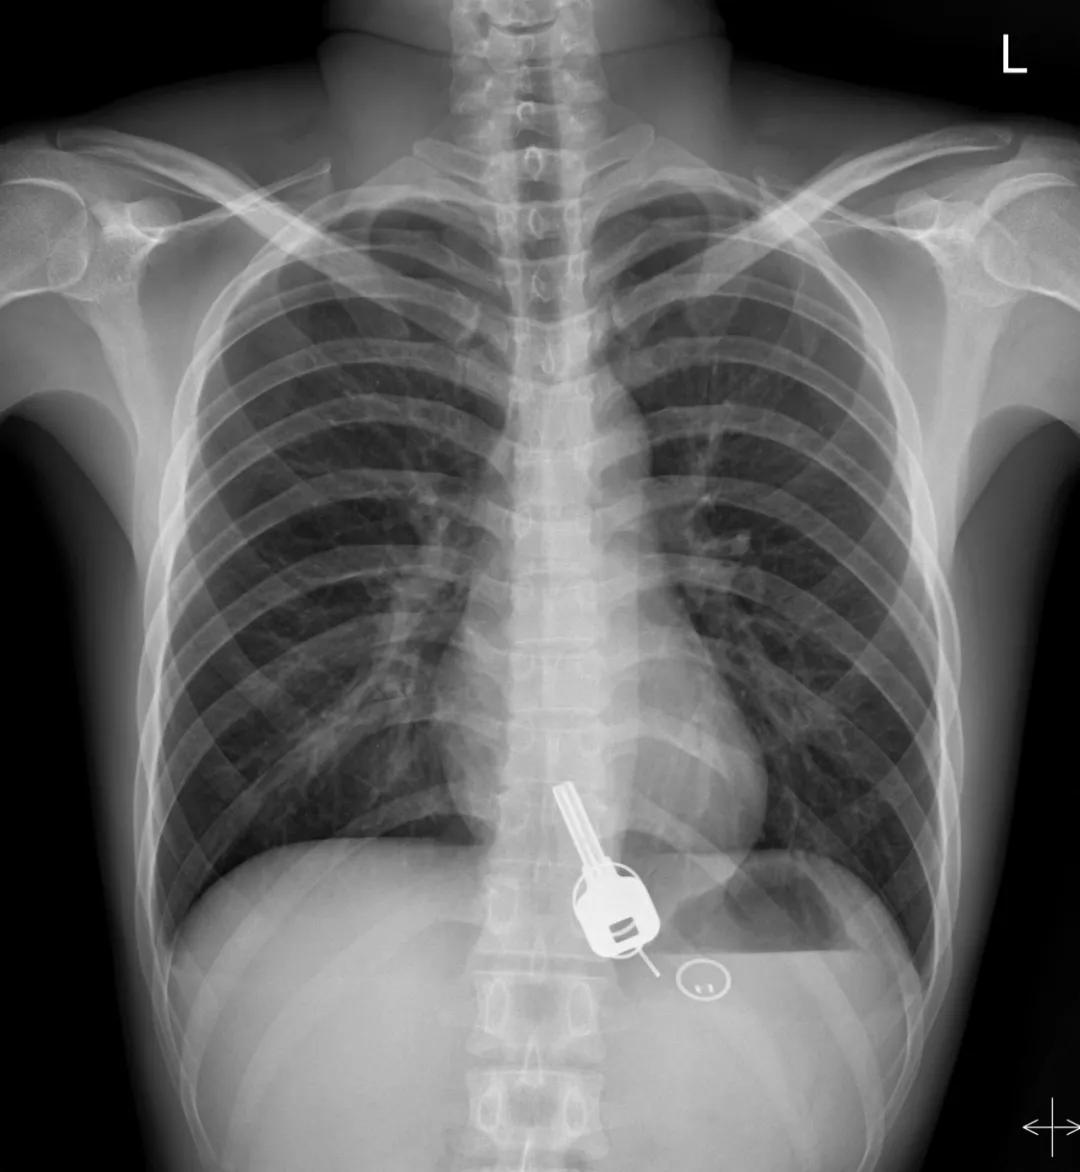

而下面東莞小哥喝酒喝到吞鑰匙

廣東東莞的常先生酒后回家找不到鑰匙,酒醒后他感到胸口疼痛,去醫(yī)院一查,發(fā)現(xiàn)一把鐵鑰匙、2個(gè)鑰匙扣、1個(gè)門禁牌清楚顯示在肚子胃區(qū)的位置上。